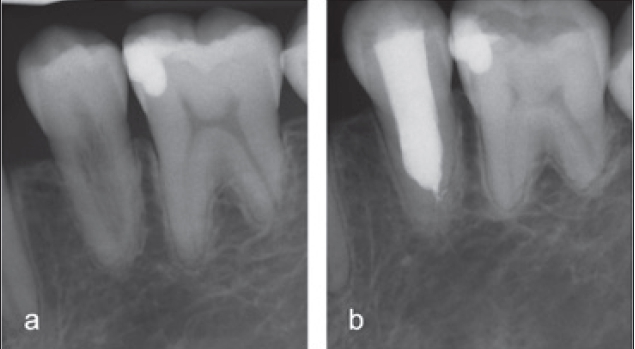

Während invasive zervikale Resorptionen in der Progressionsphase radioluzente Läsionen zeigen, stellen sich die Defekte in der anschließenden reparativen Phase radioopak dar.

Sie verläuft häufig symptomfrei und wird oft im Rahmen von Routineuntersuchungen entdeckt. Es sind in der Regel tastbare zervikale Defekte vorzufinden, die mit Granulationsgewebe gefüllt sind, welches bei Berührung stark blutet (Abb. 7a bis c). Eine zunehmende Ausbreitung des hyperplastischen Resorptionsgewebes verursacht großräumige Defekte, die sich als rötliche Verfärbungen der Zahnkrone, sogenannte Pink-Spot-Läsionen, zeigen können (Abb. 7d). Radiologisch stellt sich die invasive zervikale Resorption meist als wolkige Aufhellung im Bereich des Zahnhalses dar (Abb. 7e und f). Ein typisches Merkmal ist auch das unversehrte perikanaläre Dentin, was als „Pericanalar Resorption Resistant Sheet“ (PRRS) bezeichnet wird [25,26]. Wie bereits erwähnt, ist Prädentin äußerst widerstandsfähig gegen resorptive Prozesse und stellt sich bis zuletzt als intakte Dentinbarriere dar (Abb. 8). Die invasive zervikale Resorption verläuft in mehreren Stadien [27]. Über einen Zementdefekt (Abb. 8) dringt das entzündliche Gewebe zunächst in die Zahnwurzel ein (Initiation). Bei weiteren bakteriellen Reizen, persistierenden Krafteinwirkungen oder Gewebehypoxie breitet sich die Resorption im Zahn in alle Richtungen aus (Progression). Im Laufe der invasiven Auflösung durch das entzündliche Gewebe kommt es zu einem knochenähnlichen Remodeling von Zahnhartgewebe (Reparatur).